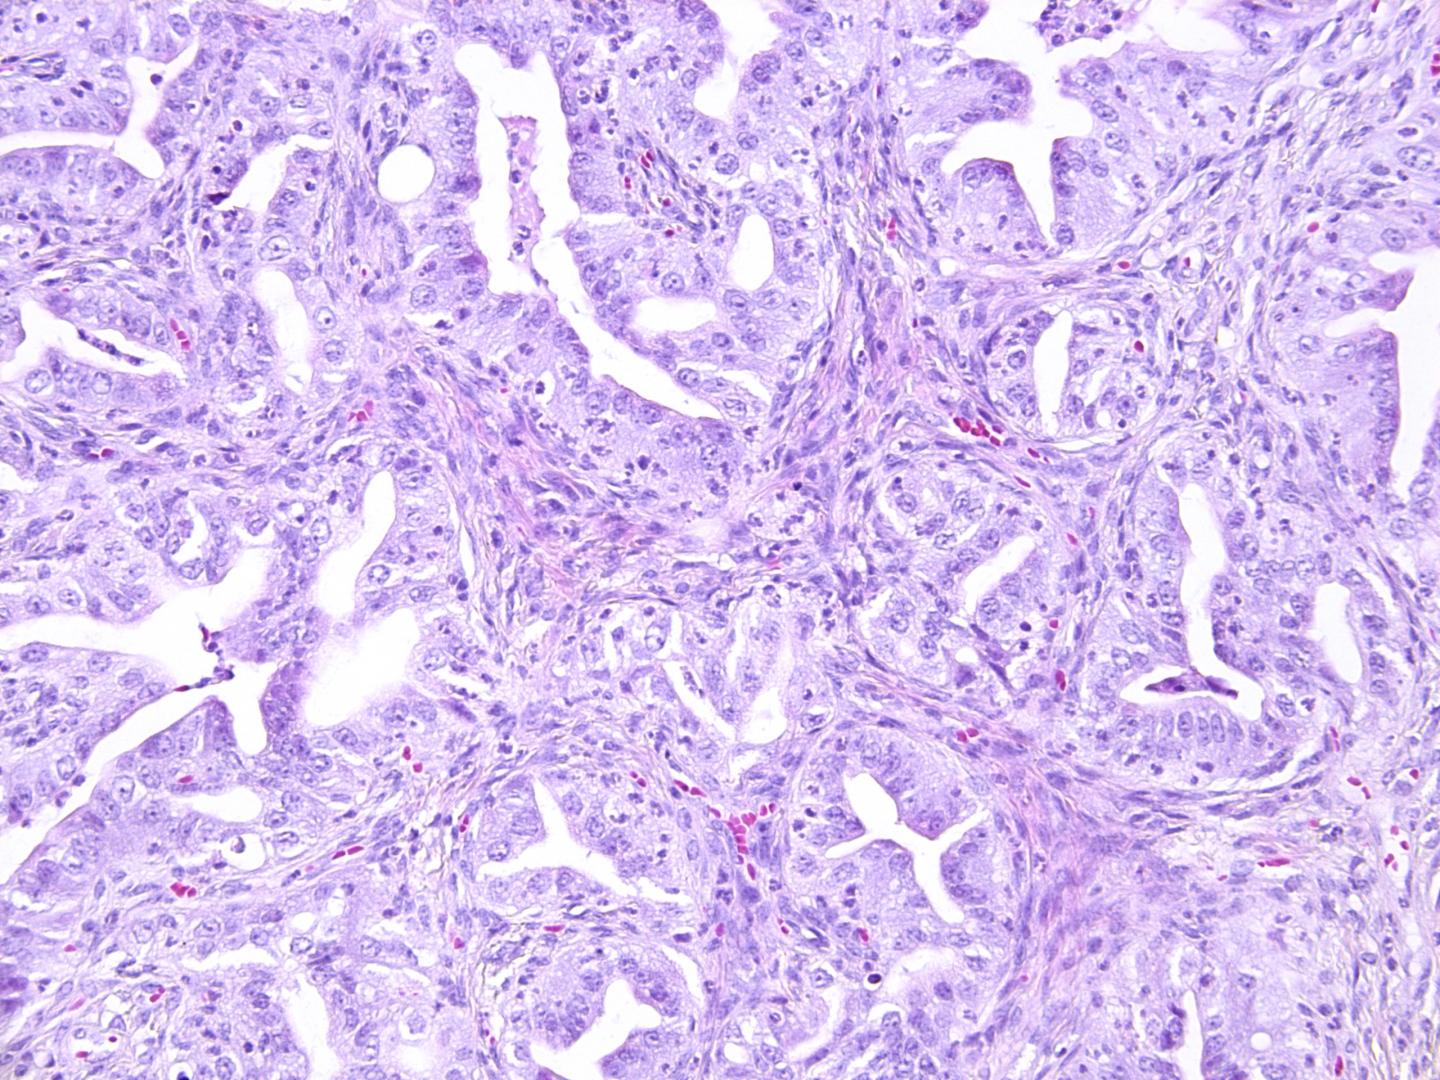

When mutations were introduced in three of the four genes, namely Trp53, Brca1 and either Nf1 or Pten, the organoids acquired characteristics of tumors, such as more densely packed cells and changes in chromosome number. In addition, when these organoids were transplanted back into mice, they developed into tumors that are similar to ovarian cancer tumors in humans.

The researchers found out that organoids from the oviduct were more likely to develop into tumors, grew faster and grew into larger tumors than the organoids from the ovarian surface epithelium. This suggests that ovarian cancer is more likely to originate in the oviduct, or the fallopian tube in humans, compared to the ovarian surface epithelium.